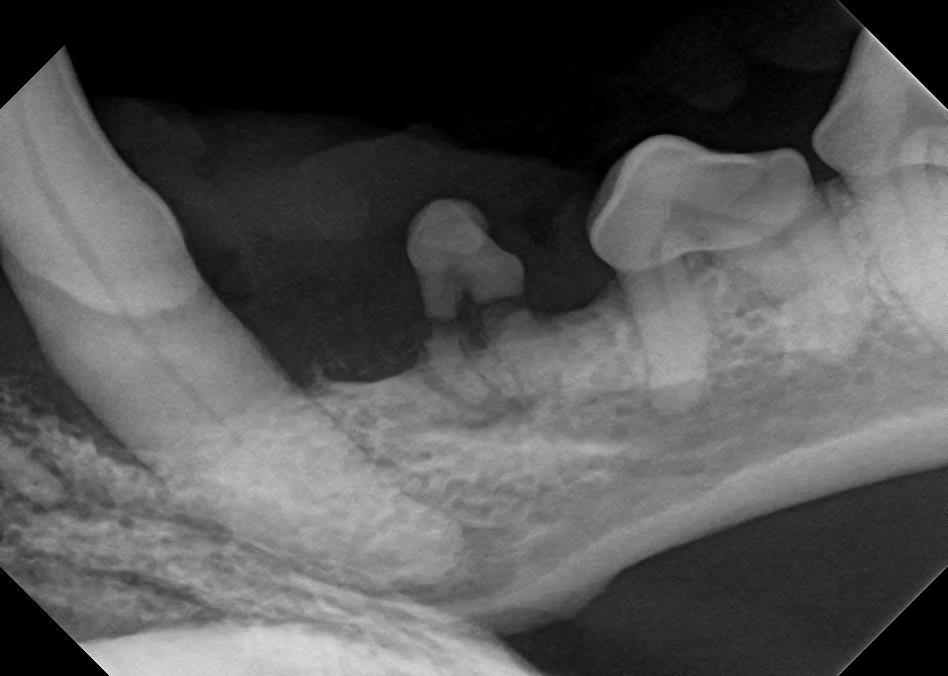

Dental X-Rays

Click on an image to learn more!